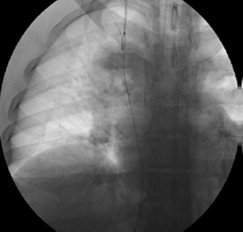

Se procedió a practicar la cavografía de control con oclusión fija en la vena cava inferior perihepática con una guía de 0,035 pulgadas hidrofílica más un catéter multipropósito (Cordis™ - Johnson & Johnson), logrando pasar a la aurícula derecha; se recuperó esta guía por la vía yugular interna con un snare o recuperador de cuerpo extraño (Merit Medical Corp.) y se extrajo por el cuello para poder tener una guía transyugular (figura 4).